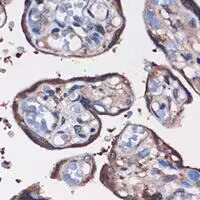

Immunohistochemical analysis of WDR61 staining in human placenta formalin fixed paraffin embedded tissue section. The section was pre-treated using heat mediated antigen retrieval with sodium citrate buffer (pH 6.0). The section was then incubated with the antibody at room temperature and detected using an HRP conjugated compact polymer system. DAB was used as the chromogen. The section was then counterstained with haematoxylin and mounted with DPX.